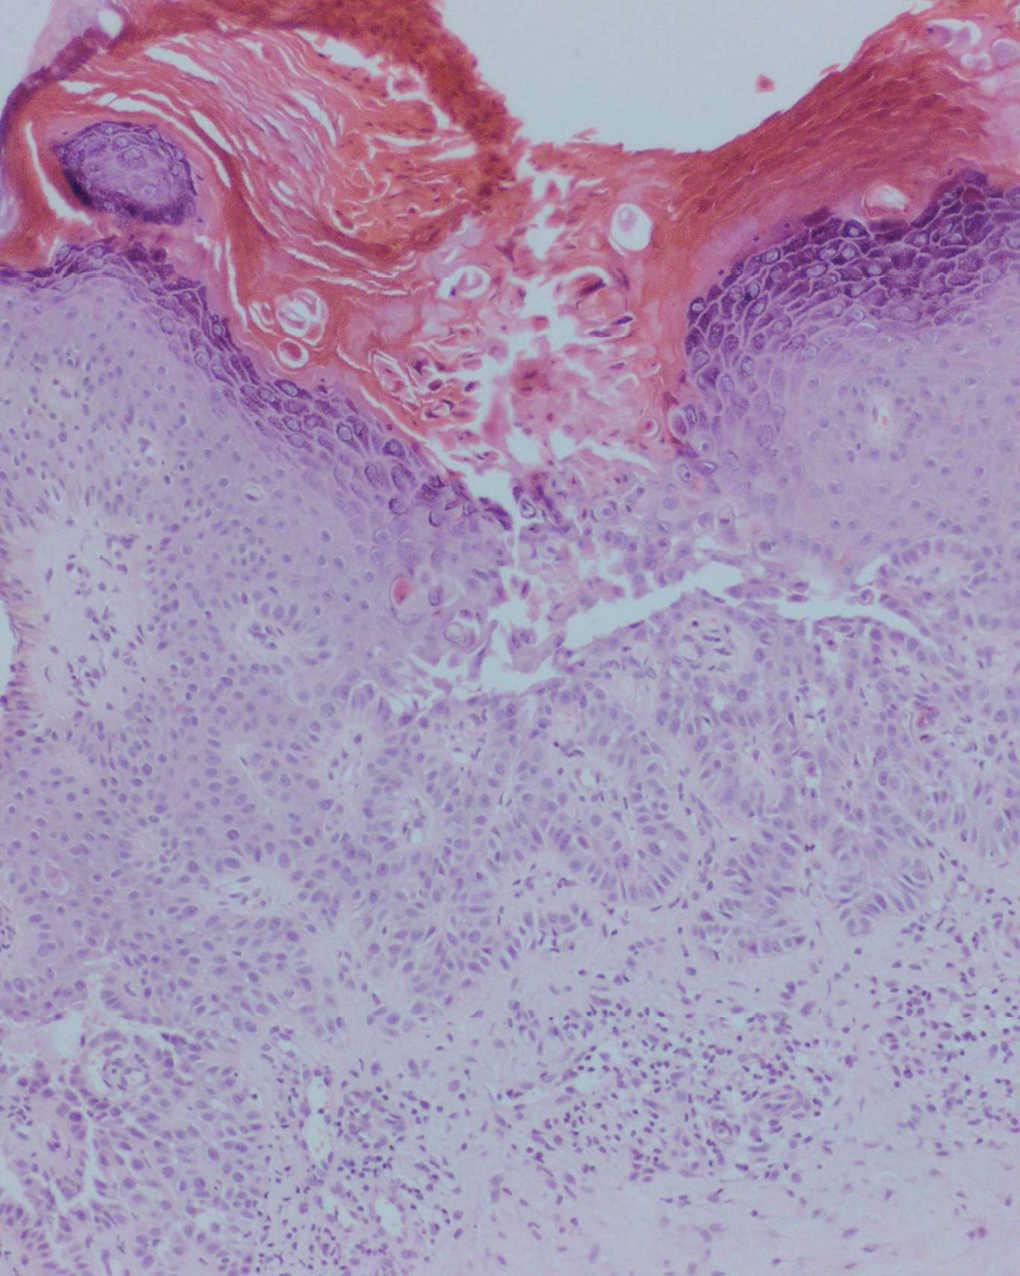

Una mujer de 21 años, sin antecedentes personales ni familiares de interés, consultó por presentar desde hacía 3 años unas pequeñas pápulas queratósicas, de coloración amarillenta-marrón-amarillenta, distribuidas linealmente a lo largo de la cara posterior de la pierna derecha. Las lesiones eran asintomáticas y no empeoraban con el sol ni con el sudor. No presentaba afectación de palmas o plantas, mucosa, ni anejos. Había recibido tratamiento con corticoides tópicos que empeoraban las lesiones (fig. 1).

Fig. 1.--Lesiones formando un patrón lineal.